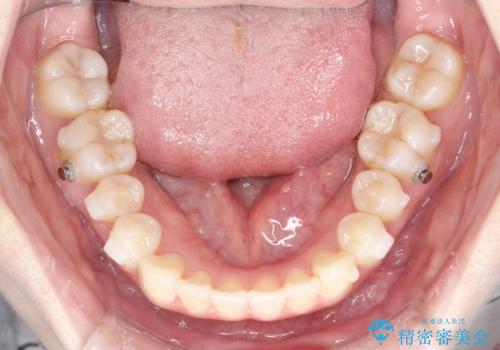

【インビザライン】矮小歯を有する方の治療②

- 前歯の凸凹を主訴に来院されました。

左上の前歯が元々小さいため、前歯の真ん中が揃わないことを伝えた上で矯正治療を開始しています。

スペースを作るために遠心移動ろIPRをおこなて治療を行いました。